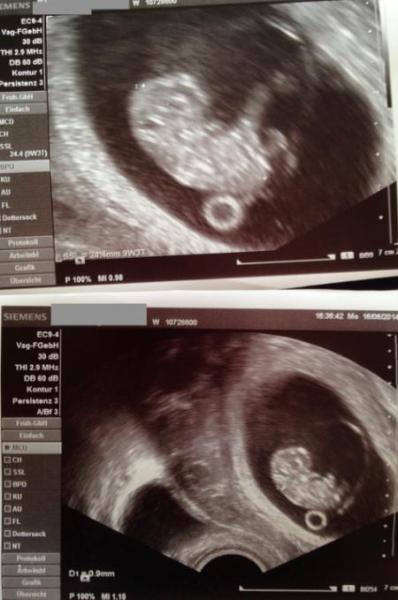

ooooh war das schöööön das kleine Püppchen ist 2,4 cm laut US wäre ich nen Tag weiter aber wir lassen den ET mal beim 17.1. - Nackenfalte hat er auch geschaut und da ist alles paletti soll jetzt aber mit diesen Handschuhen den pH Wert messen der is immer etwas niedrig aber ich glaube das hatte ich bei meiner Tochter auch und prompt wurde ich heute auf meinen Bauch angesprochen und ich kann nicht lügen jetzt ists also vorbei mit geheim halten

so noch ein letzter Versuch mal schaun ob das Foto klappt